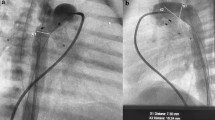

Representative images of stenting with Pul-Stents. Left pulmonary artery stenosis (a) before and b after stenting in a 7-year-old boy (weight: 21 kg) with postoperative status of tetralogy of Fallot (model M with 16 mm BIB balloon). Right pulmonary artery stenosis (c) before and (d) after stenting in a four-year-old girl (weight: 17 kg) who underwent a Glenn procedure (model S with 10 mm EV3 balloon)

After stent implantation, 97% (34/35) of patients had a 50% increase in the minimal lumen diameter of the stenosed segment (Fig. 2), and 77% of biventricular patients (23/30) had a 50% decrease in the pressure gradient across the stenosed segment. Overall, the mean minimum diameter of the pulmonary artery stenosis increased from 3.9 ± 1.7 mm to 8.9 ± 2.1 mm (P < 0.001). Among the biventricular patients (n = 30), the mean systolic pressure gradient across the pulmonary artery stenosis decreased from 30.1 ± 12.2 to 9.7 ± 9.5 mmHg (P < 0.001), and the right ventricular-to-aortic pressure ratio decreased from 0.57 ± 0.14 to 0.43 ± 0.12 (P < 0.001). For patients with a postoperative cavopulmonary anastomosis (n = 5), the mean superior vena cava pressure after stenting decreased from 17.0 ± 1.9 to 14.0 ± 0.7 mmHg (P = 0.046).

Stenting a left pulmonary artery (LPA) stenosis with Pul-Stents in a 6-year-old boy (weight: 19 kg) after a Fontan procedure. a A severe LPA stenosis with atresia tendencies. b Initial stenting with the Pul-Stent (model S) with a 6-mm EV3 balloon after sequential dilation with a series of coronary balloons. c Angiography at the 4-year follow-up did not identify stent stenosis, distortion, or fracture. d Further dilation of the stent with a 10-mm EV3 balloon resulted in mild stent shortening without stent fractures or migration

Ten patients underwent stent re-dilation (model S = 9, model M = 1) after a mean follow-up of 3.8 ± 2.0 years after implantation, improving the stent diameter from, on average, 7.0 ± 2.7 mm to 10.8 ± 1.6 mm (P < 0.001). Furthermore, in the biventricular patients (n = 7), the gradient pressure changed, on average, from 25.0 ± 18.3 mmHg to 7.3 ± 4.9 mmHg (P = 0.036). Repeat dilations were primarily indicated for arterial segments with a larger diameter or residual waist, except for one patient with an occlusive left pulmonary artery after the Glenn procedure; this patient had significant intimal proliferation and severe in-stent stenosis at the 1-year follow-up. Furthermore, despite receiving aspirin and warfarin after the initial procedure and a successful re-dilation, the stent became obstructed again, but a third intervention was abandoned. Stent fractures or migrations were not observed on further dilation (Fig. 3).

Stenting of a right pulmonary RPA stenosis in a 6-year-old boy (weight: 18 kg) after the surgery of tetralogy of Fallot. a A severe stenosis of the RPA bifurcation. b Initial stenting with a Pul-Stent (model S, length: 15 mm) with a 12-mm EV3 balloon without jailing the right upper pulmonary artery branch. c Angiography at 4-year follow-up did not identify stent stenosis or fracture, and the right upper pulmonary artery branch still filled freely through the side of the stent. d A “dog boning” stent with significant shortening after further dilation with a 15 mm × 40 mm non-compliant balloon and a 14 mm × 40 mm high-pressure balloon for the resistant stenosis. Also, a Cheatham-Platinum stent is present in the left pulmonary artery, implanted during a previous surgical repair

One model S stent with an unexpanded length of 15 mm had significant shortening of the overall length after re-dilation with an oversized non-compliant balloon (15 mm × 40 mm) and a high-pressure balloon (14 mm × 40 mm) for a resistant residual waist. Nonetheless, it covered the entire lesion with a good radial force and no recoil (Fig. 4).